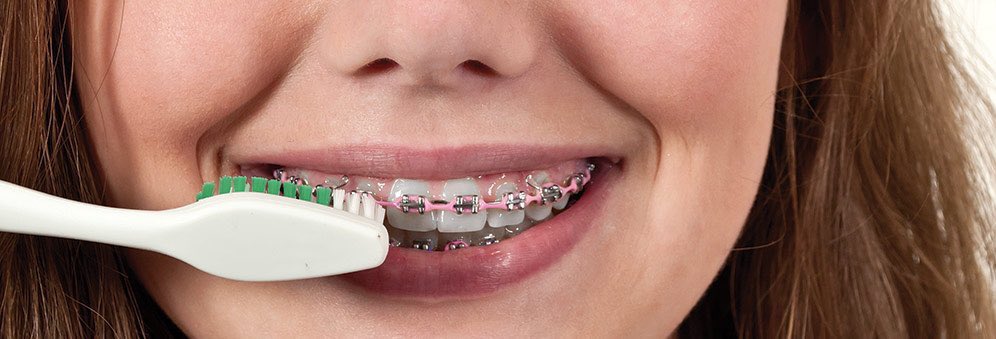

٩- الاشخاص الذين يستعملون الأجهزة التقويمية يجب أن يراعو عناية فائقة بالأسنان واللثة لوجود اجهزة يعلق بها كمية أكبر من البلاك وبالتالي تضاعف عدد البكتيريا المسببة للتسوسات والتهابات اللثة (٩)=

الوقاية: